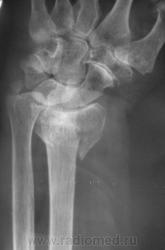

Случай 2.  Пациент направлен врачом хирургом на рентгенографию лучезапястного сустава.

Случай 3. Пациент направлен врачом хирургом на рентгенографию лучезапястного сустава.

А вот по-поводу второго случая: перелом луча в "типичном" месте, только вот смущает ладьевидная кость - какая-то она патологическая, имеется участок разряжения костной ткани в проекции головки кости или я ошибаюсь?